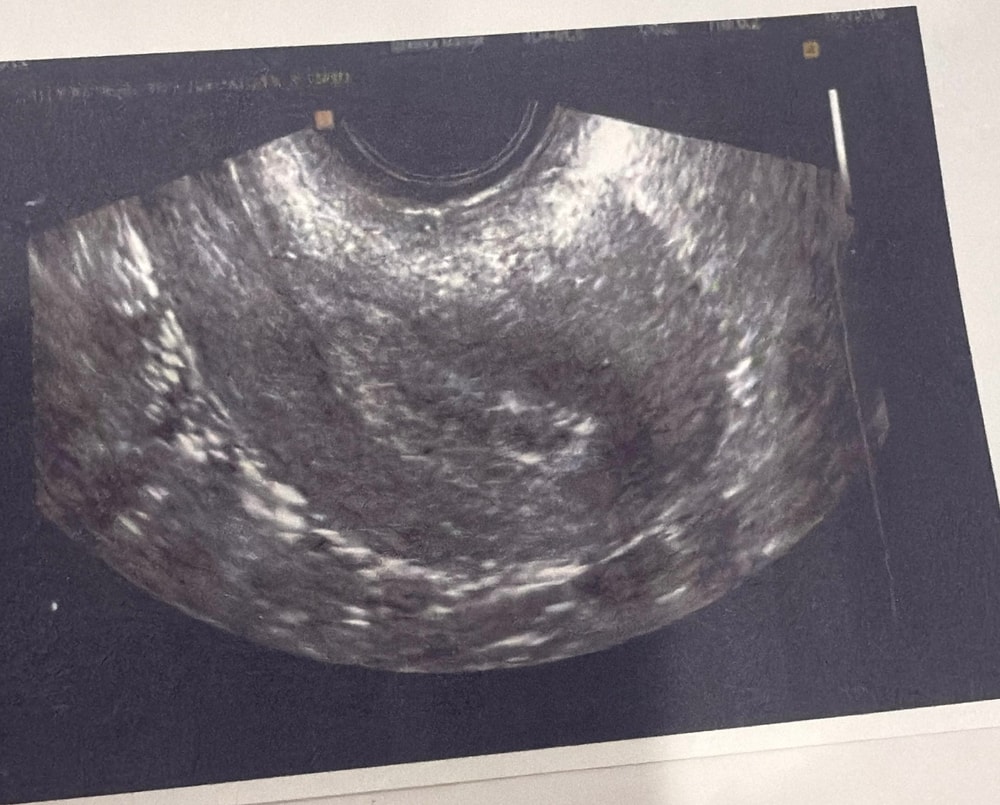

Сделала узи 6 ноября, в полости матки анэхогенное включение диаметром 3,4 мм с гиперэхогенным контуром? Это и есть плодное яйцо? Тесты на беременность положительные, 30 октября сдавала хгч показал 58.7, 7 ноября сдала еще хгч, жду результат

Да, такое на раннем сроке бывает - плодное яйцо ещё очень маленькое, и пока не видно эмбриона. Главное, что ХГЧ растёт и тесты положительные.

Скорее всего это и есть пя